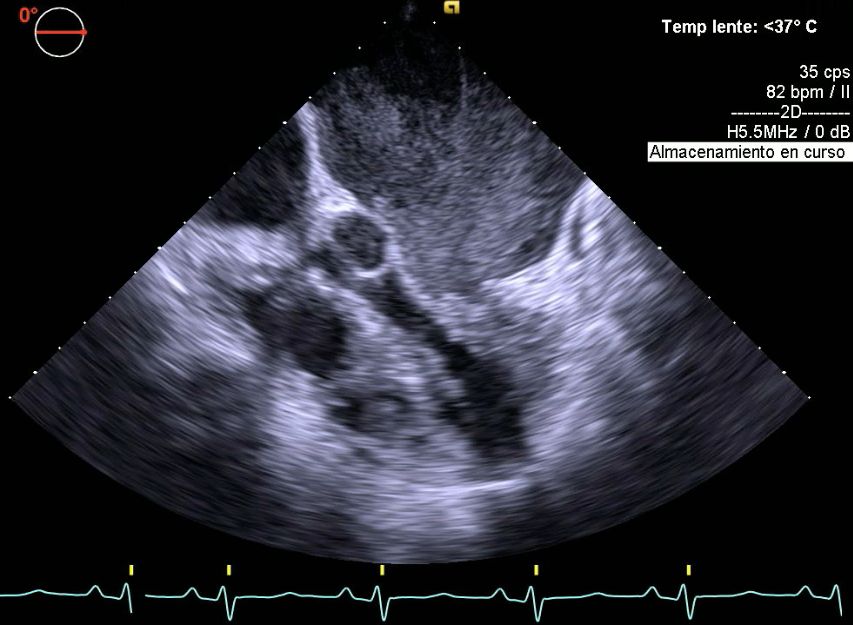

• Ecocardiografía

• Ecocardiograma

• Centro de Especialidades Médicas y Odontológicas Ecocardiograma  •

• Star Médica Mérida Consultorio 526 Ecocardiograma + doppler color  •